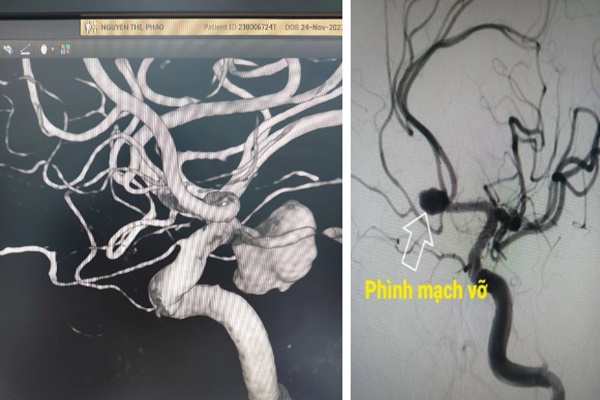

Bác sĩ Lưu Thiện Kiệt, bác sĩ phẫu thuật thần kinh tại bệnh viện Đa khoa Quảng Điền, Đài Loan, Trung Quốc cho biết, bệnh nhân Điền nhập viện trong tình trạng nguy kịch. Qua thăm khám, bác sĩ phát hiện bệnh nhân mắc chứng phình mạch máu não (phình động mạch nội sọ), túi phình động mạch có kích thước 2cm đã bị vỡ và gây xuất huyết não. Bác sĩ Lưu cho biết, bệnh nhân có tiên lượng xấu, tỉ lệ tử vong cao.

Bác sĩ Lưu giải thích phình động mạch nội sọ (phình động mạch não) là tình trạng các túi phình phát triển trong động mạch máu não.

Theo phòng khám Mayo Clinic, Mỹ, phình động mạch não thường phát triển ở những vùng mạch yếu như các đoạn mạch rẽ nhánh, tạo thành các túi phình mạch máu. Khi kích thước của các túi phình tăng lên, thành mạch dần mỏng đi và có thể làm tăng nguy cơ vỡ túi phình động mạch. Vỡ túi phình động mạch não sẽ gây xuất huyết trong não và có thể dẫn đến đột quỵ não.

Hình ảnh mô tả túi phình động mạch não. (Ảnh minh họa)